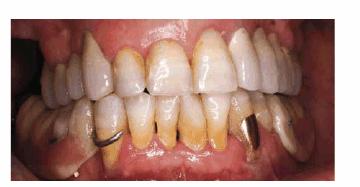

Figure 29-4A shows a 74-year-old woman who was dissatisfied

with her smile but was not sure if she wanted considerable changes made. Her

chief concern was that she did not like her malpositioned lower incisors.

Orthodontics was not an option owing to the cost and length of treatment time.

Cosmetic contouring of the mandibular teeth was selected as a compromise

treatment because of its conservative approach (Figure 29-4B). The patient liked the changes in the lower

teeth and subsequently asked about options for improving the maxillary teeth.

Finances remained an issue, so cosmetic bonding was selected as the treatment

plan of choice. Figures 29-4C, and 29-4D show the patient's maxillary teeth before and after

cosmetic bonding.

Figure 29-4A: This 74-year-old woman was dissatisfied with the appearance of her teeth.

Figure 29-4B: Cosmetic contouring was done to make the mandibular teeth appear straighter; the maxillary incisors were direct bonded with composite resin.

Figure 29-4C: Although a compromise to full restorative esthetics, just treating a limited amount of anterior teeth can satisfy the older patient.

Figure 29-4D: At 90 years of age, this patient is still motivated to improve her smile-now with porcelain laminates. Although the treatment is still a compromise because of her inability to sit through many long appointments, she is slowly involving more teeth in the restorative process.